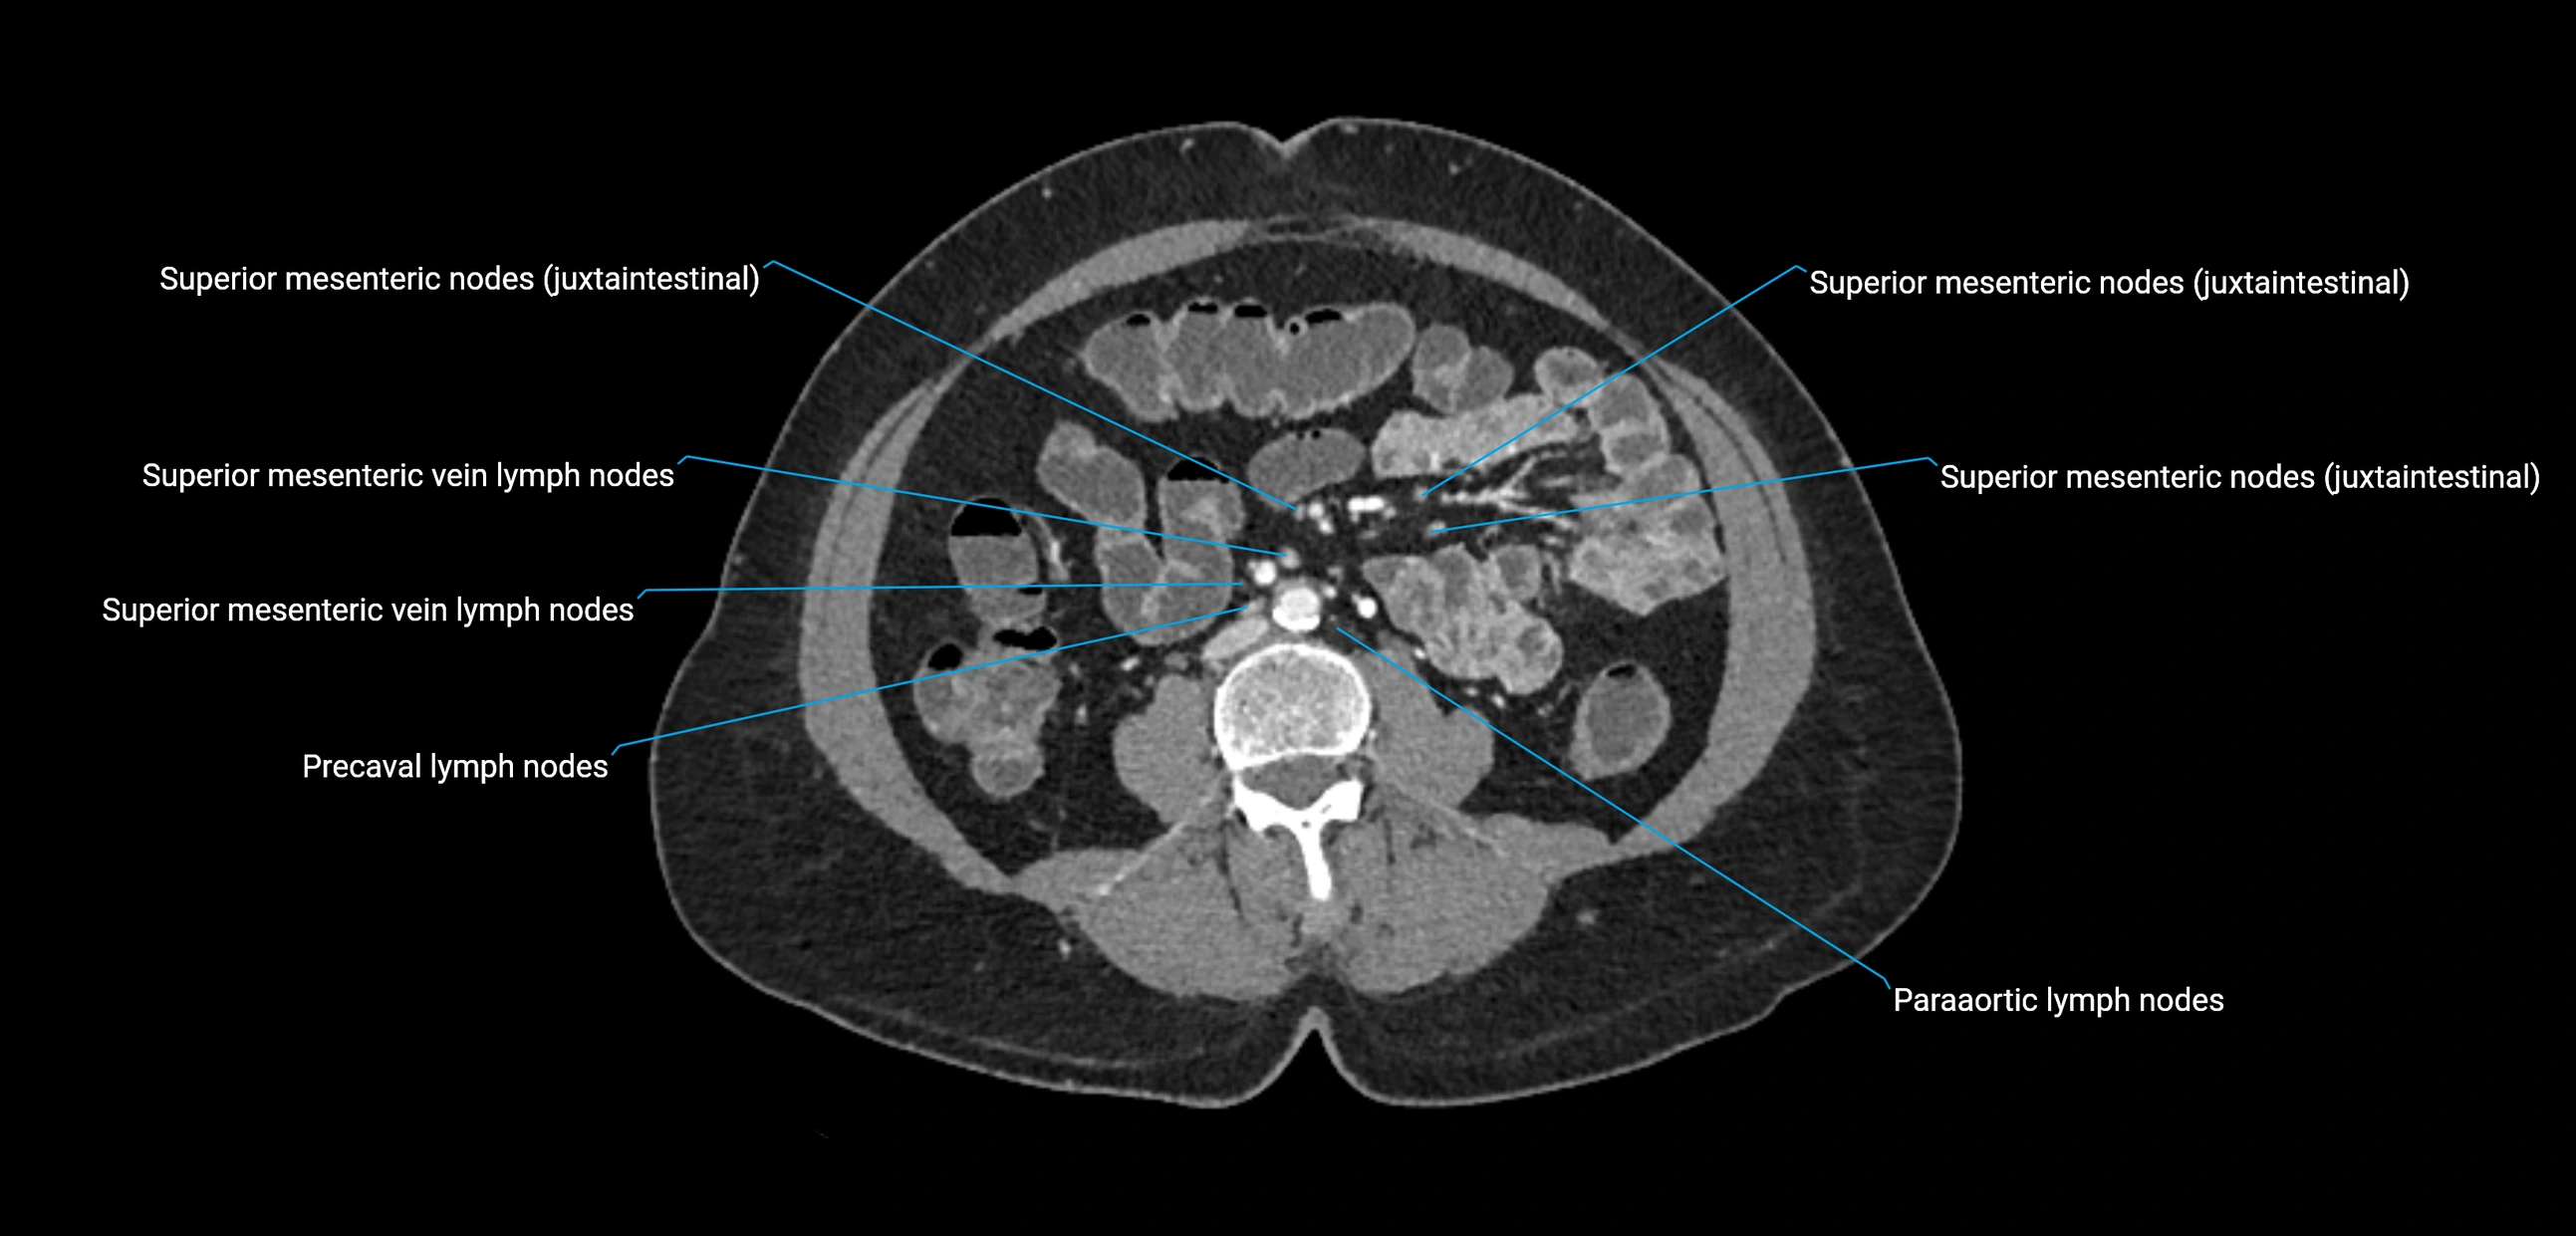

CT Appearance

CT Pre-Contrast:

• Nodes appear as soft-tissue density nodules adjacent to the aorta and IVC

• Calcification may be seen in chronic infections (e.g., tuberculosis)

CT Post-Contrast:

• Normal nodes enhance homogeneously

• Malignant nodes may show heterogeneous enhancement, central necrosis, or conglomerate formation

• Size >1 cm short axis is suspicious, though morphology and distribution are equally important